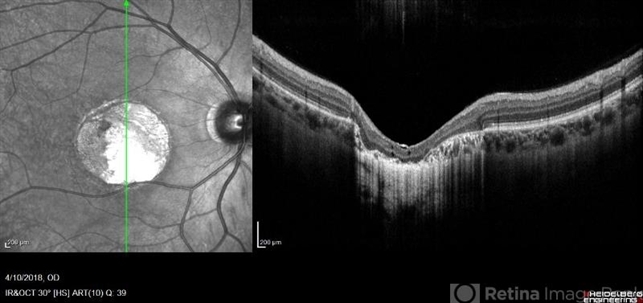

- macular dystrophy, central areolar choroidal dystrophy (CACD), retinal dystrophy, hereditary retinal dystrophy

- Heidelberg Spectralis

- Right fundus OCT of a 35-year-old man with central areolar choroidal dystrophy, BCVA is 6/60